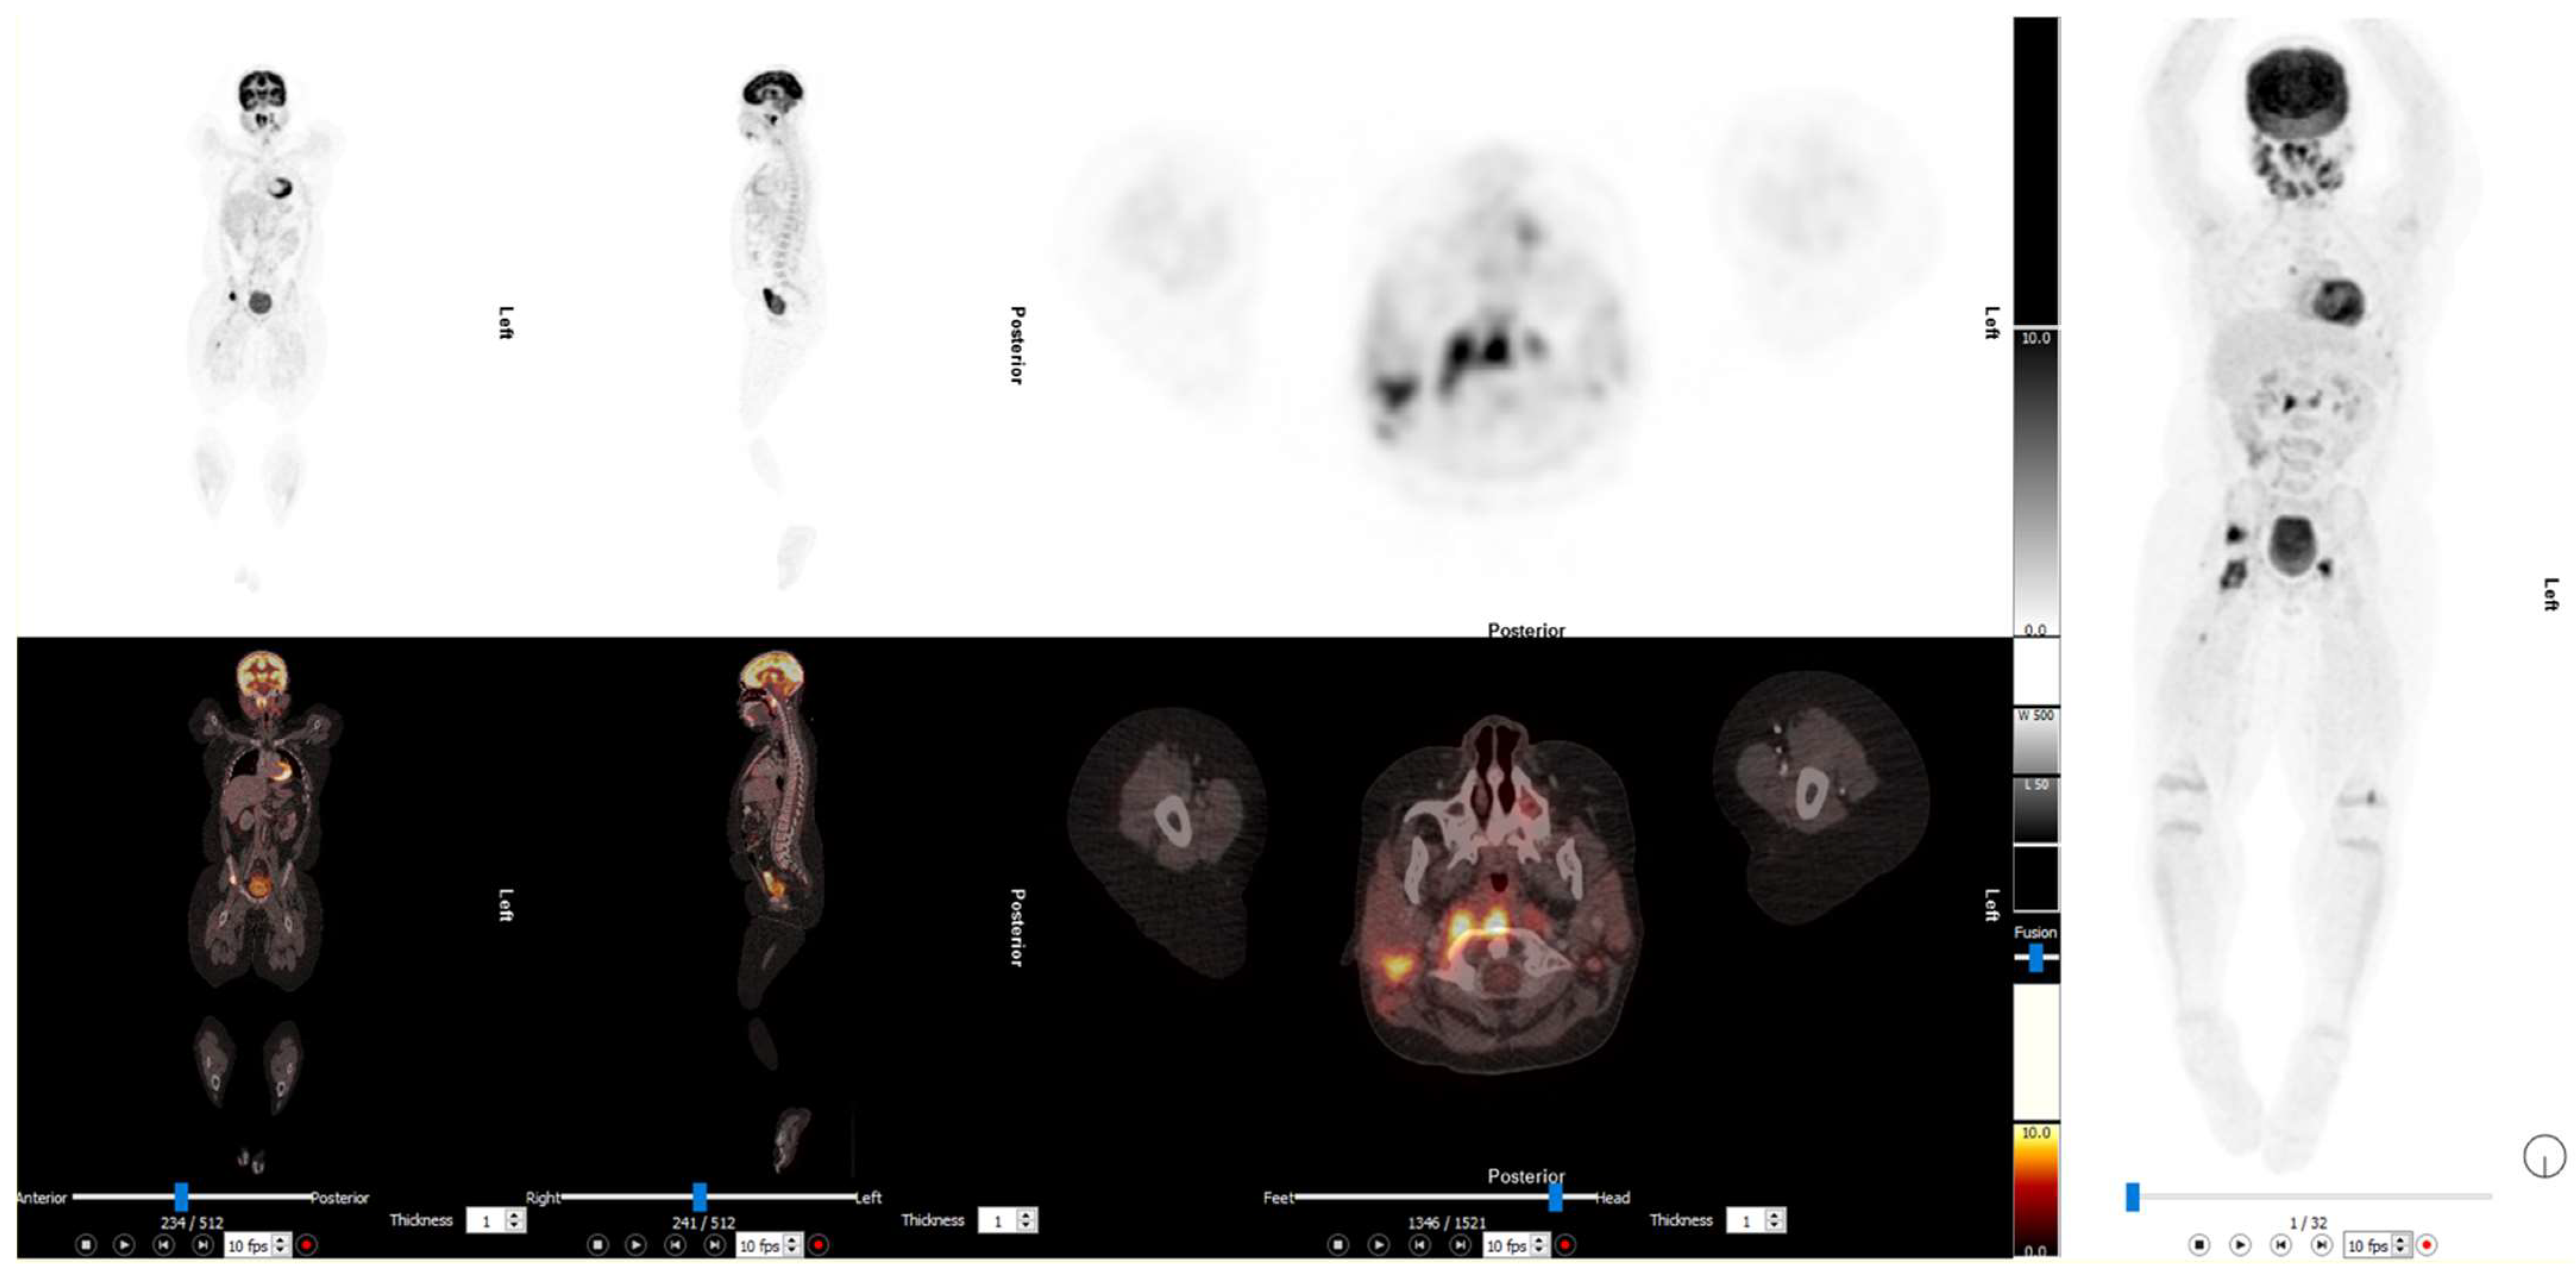

2. Paediatric Lymphoma

3. Neuroblastoma

3.1. 2-[18F]FDG PET/CT in Neuroblastoma

3.2. [124I]mIBG PET/CT in Neuroblastoma

3.3. [68Ga]DOTA-SSA PET/CT in Neuroblastoma

3.4. [18F]F-DOPA PET/CT in Neuroblastoma